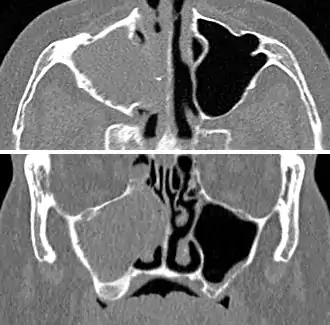

Frontal sinusitis

X-ray of left-sided maxillary sinusitis marked by an arrow. There is lack of the air transparency indicating fluid in contrast to the other side.